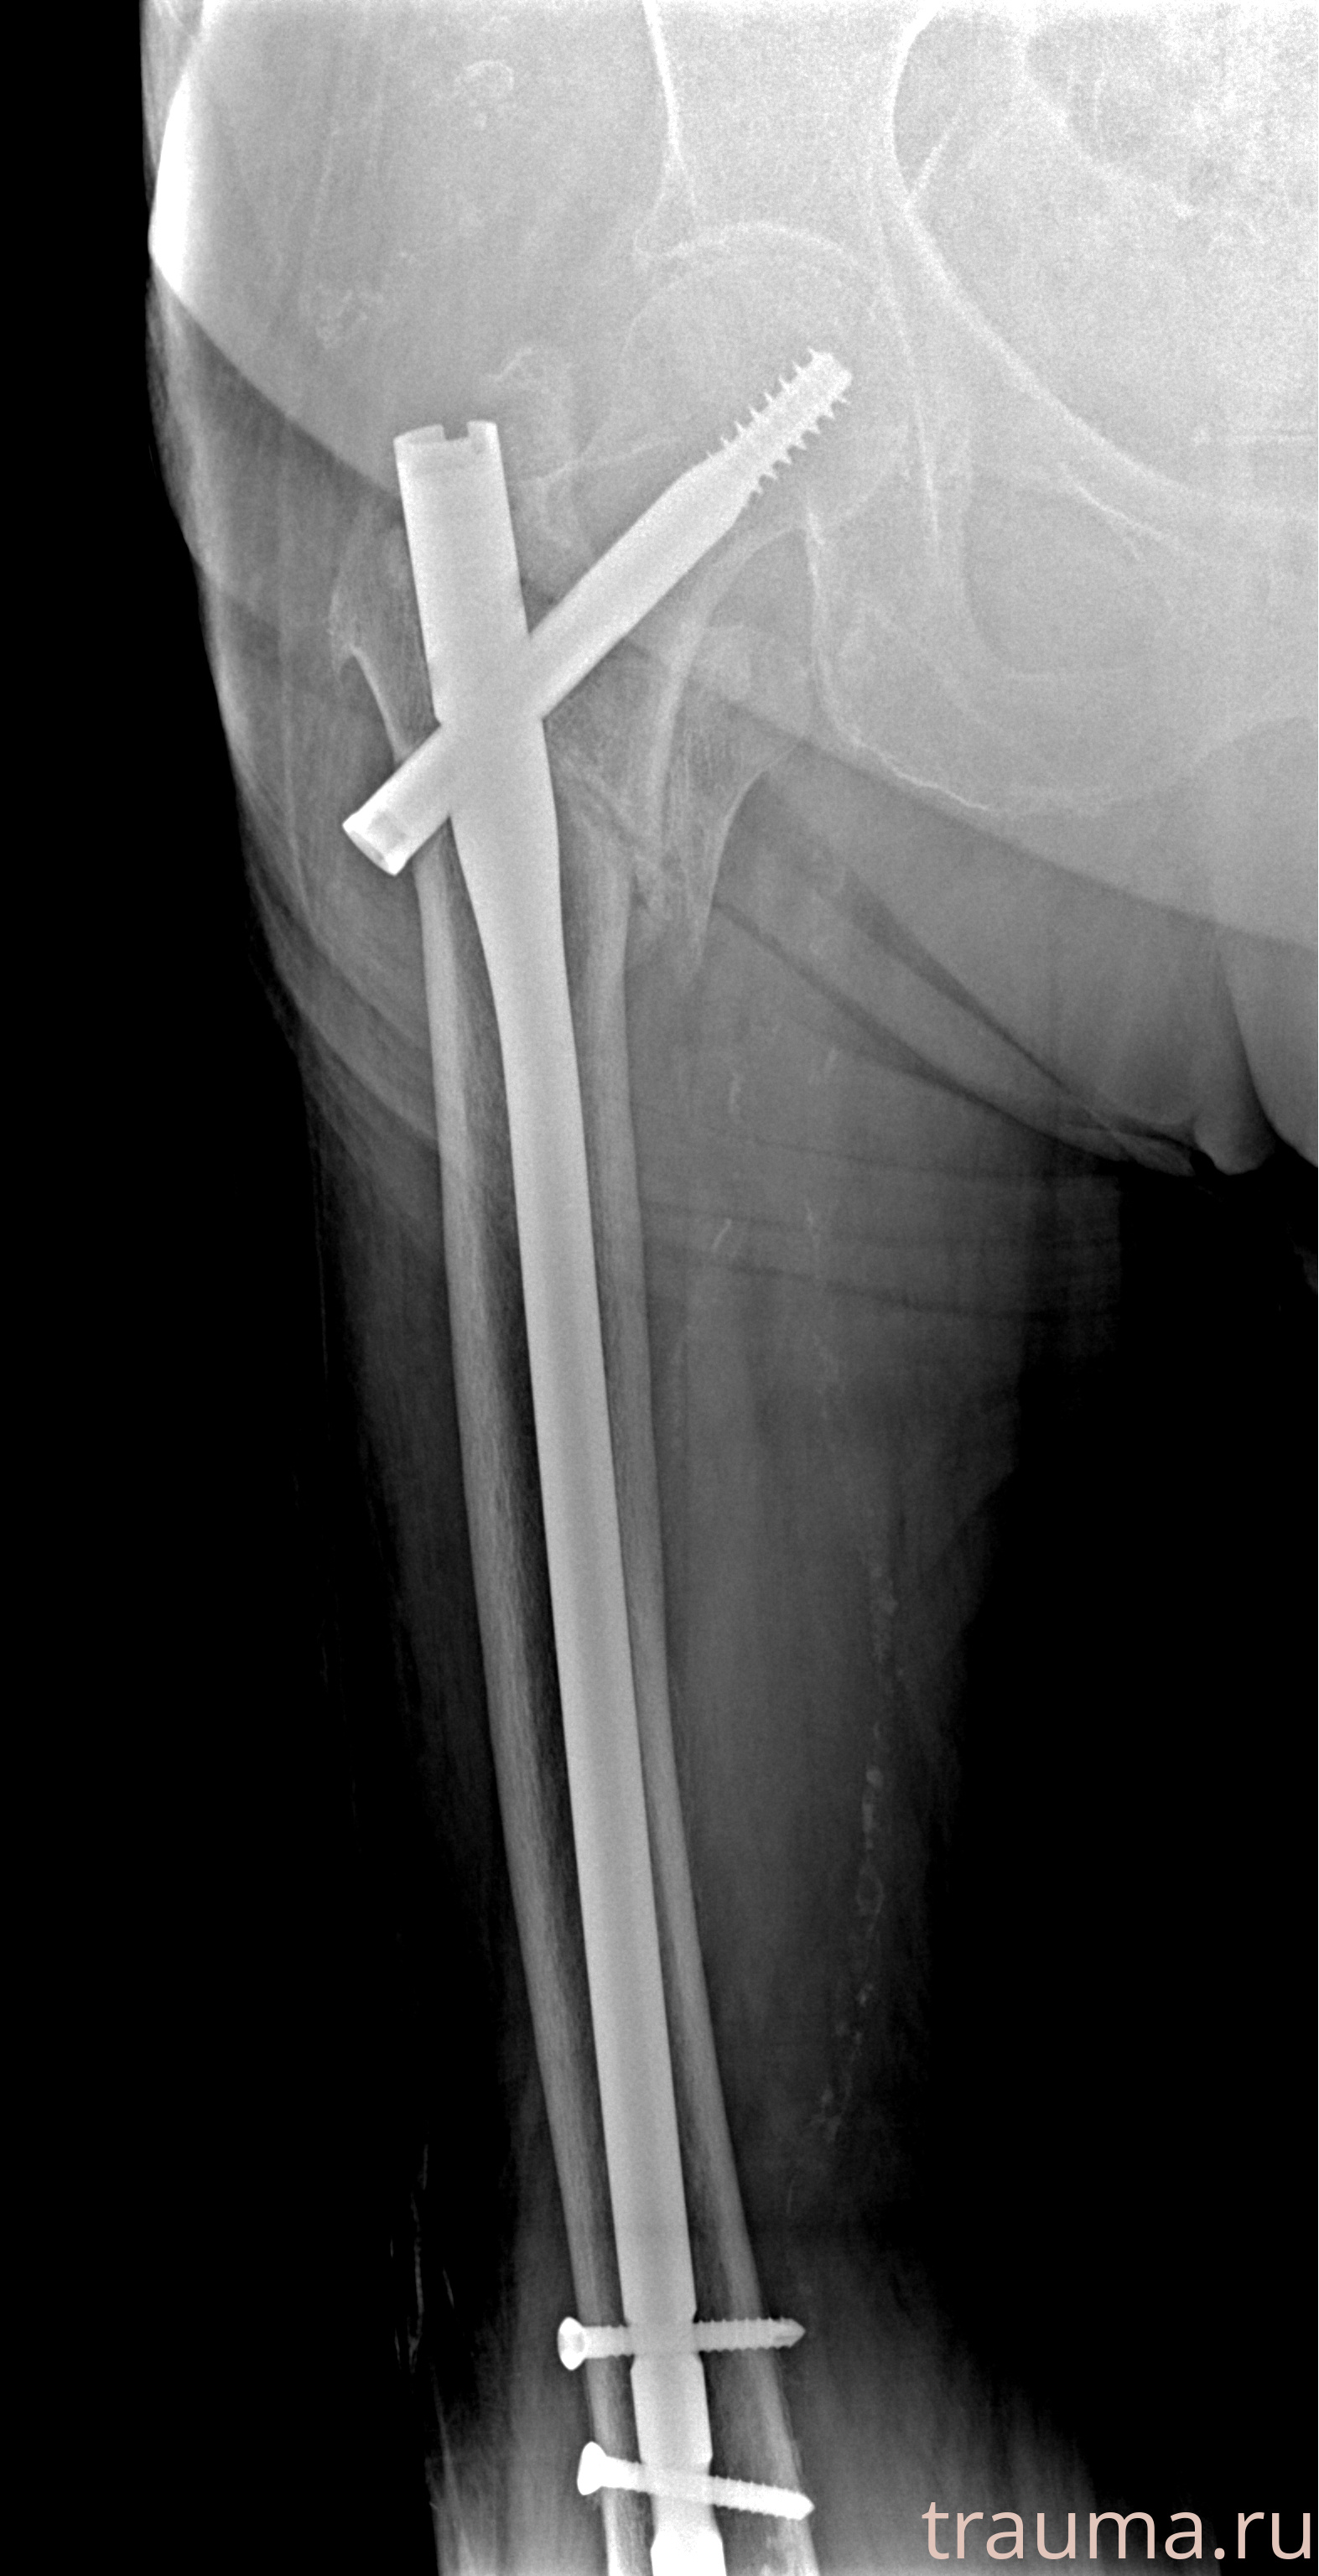

Рентгенограммы

Рентген на дому: по вашему адресу приезжает врач-рентгенолог, травматолог-ортопед с мобильным рентгеновским аппаратом, проводит диагностику травмы или заболевания, делает необходимые рентгенограммы, дает рекомендации по дальнейшему лечению. Получить качественные снимки в домашних условиях возможно благодаря уникальной методике, разработанной МосРентген Центром для института  Склифосовского